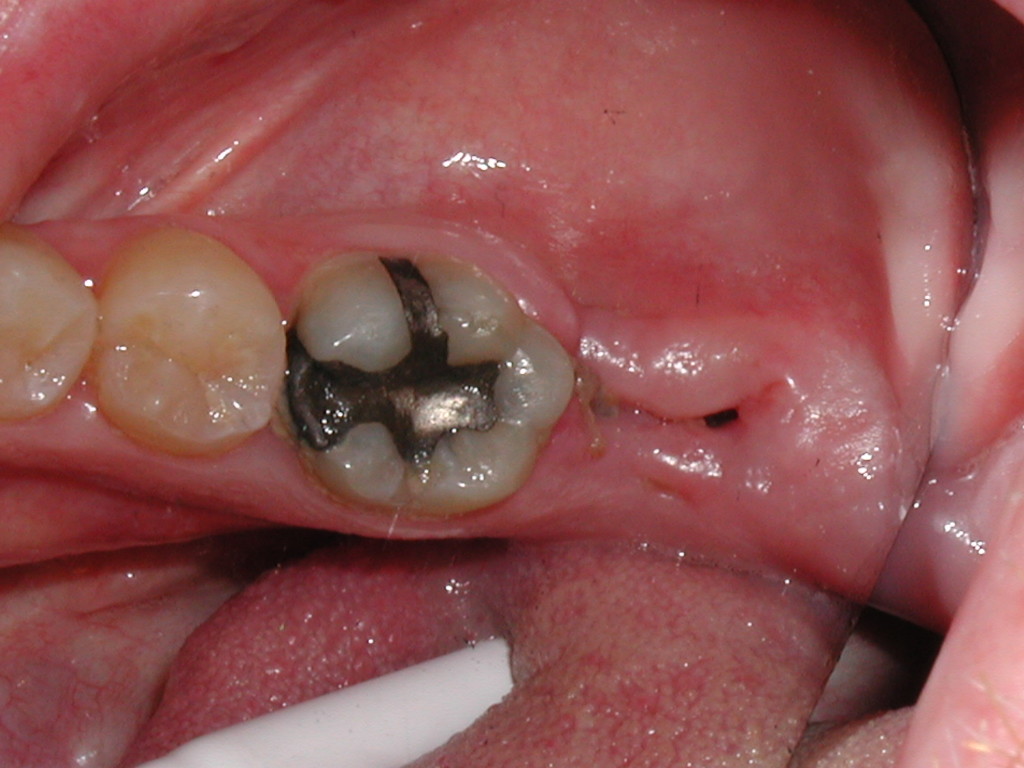

Kıymetli Hastamız! Kliniğimizde cerrahi işlemler dışında diş beyazlatma, porselen kaplama, gülüş tasarımı, tedavi (diş dolgusu, kanal tedavisi), hareketli (total ve parsiyel protezler), hibrid (implantüstü) ve sabit protezler (porselen, zirkon, lamina) ile temel dişeti hastalığı tedavilerini (diş taşı temizliği, küretaj) de yapmaktayız. Sağlıklı günler dileğiyle!